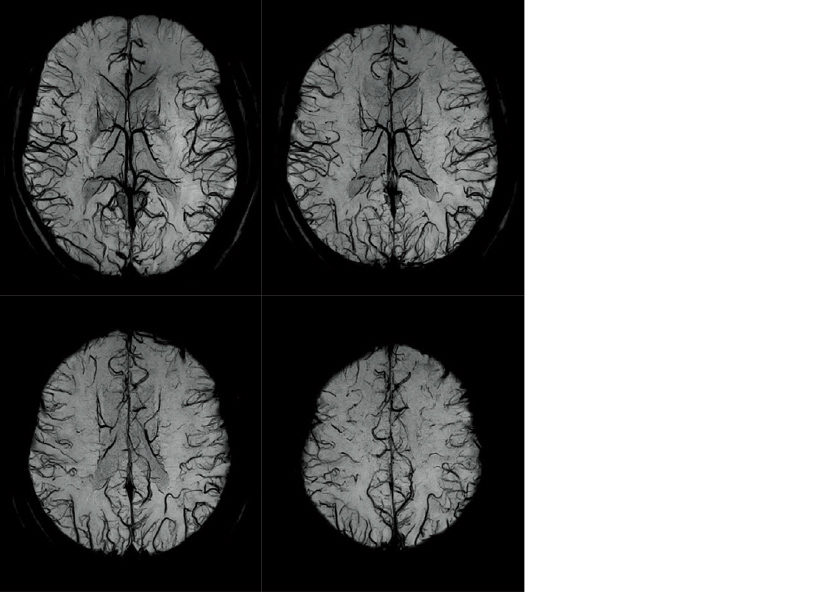

Effects of RADAR in TOF MRA and GrE T2*WI

RADAR has been applied to GrE sequences using a high-precision signal correction technology. This has enabled the combined use of RADAR in all sequences required for routine head examinations.

Examples of BSI (minP) images